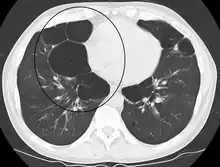

- Axial CT image of the lung of a person with end-stage bullous emphysema

- Very severe emphysema with lung cancer on the left (CT scan)

A chest X-ray and complete blood count may be useful to exclude other conditions at the time of diagnosis.[82] Characteristic signs on X-ray are hyperinflated lungs, a flattened diaphragm, increased retrosternal airspace, and bullae, while it can help exclude other lung diseases, such as pneumonia, pulmonary edema, or a pneumothorax.[83] A high-resolution CT scan of the chest may show the distribution of emphysema throughout the lungs and can also be useful to exclude other lung diseases.[25] Unless surgery is planned, however, this rarely affects management.[25] A saber-sheath trachea deformity may also be present.[84] An analysis of arterial blood is used to determine the need for oxygen; this is recommended in those with an FEV1 less than 35% predicted, those with a peripheral oxygen saturation less than 92%, and those with symptoms of congestive heart failure.[24] In areas of the world where alpha-1 antitrypsin deficiency is common, people with COPD (particularly those below the age of 45 and with emphysema affecting the lower parts of the lungs) should be considered for testing.[24]